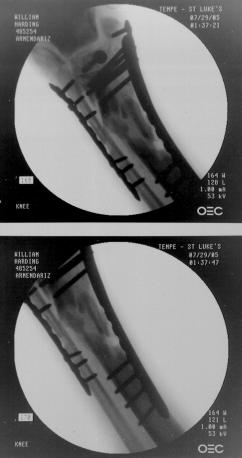

Pre-corrective surgery X-Rays of the damaged right & left legs / ankles

These x-rays were taken at Dr Armendariz’s office, just prior to performing any corrective surgery. As can be seen in these images,

there was no tibia bracing provided by Dr. Keller. Liam was released from Dr Keller’s care with instructions that full weight bearing could

be accomplished within 2 months of Keller’s last surgical procedure. The best example to examine is the second image (from the left) of the

top how. Notice how the bones that should be aligned with the tibia are in fact on the other side of the leg. The third image shows how badly

Liam’s left foot was twisted as a result of the pool placement of the external fixation. What is not obvious is that the screw at the bottom

of the plate on the right fibula missed being screwed into the plate.